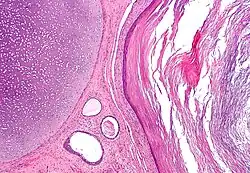

Todos los animales más complejos que las esponjas poríferas producen dos o tres capas de tejidos primarios. Los animales con simetría radial, como los cnidarios, tienen dos, denominadas ectodermo y endodermo. Los animales con simetría bilateral producen una tercera capa situada entre las dos anteriores, el mesodermo. Las capas germinales originarán los tejidos y órganos durante el proceso de organogénesis.

- Ectodermo: Es la capa germinal más externa. Es el origen de la piel y el tejido nervioso, el tubo digestivo superior (estomodeo), la epidermis y sus anexos (pelo y uñas) y las glándulas mamarias.

- Mesodermo: Es la capa germinal media. Se origina a partir de la masa celular interna y se sitúa entre el endodermo y el ectodermo. Es el origen del sistema esquelético, los músculos, el sistema circulatorio y el aparato reproductor.

- Endodermo: Es la capa germinal más interna. Aparece siempre cuando una capa de células se proyecta hacia afuera a partir de la masa celular interna que crece alrededor del blastocele. Es el origen del intestino, el hígado, el páncreas, los pulmones, los riñones, y la mayor parte de órganos internos.